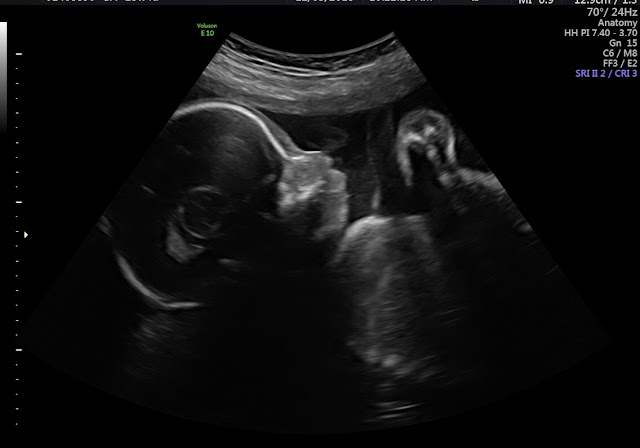

27 weeks with Rose

On Monday, I had my 27 week doctor appointment even though I was technically only 26 weeks 4 days along. According to their scale weigh 105.0lbs which is up almost 3 pounds since my last appointment 3 weeks ago. My blood pressure was 114/66. Baby B weighed 2lbs 2oz which is one ounce more than Landon weighed when he was born (at 27 weeks 5 days!) Baby is now head down which is much more comfortable for me and his heart rate was 148 beats per minute.

In other not so great news is my cervix has become significantly shorter this appointment than last time. We will be checking it again in two weeks, but it is still closed which is obviously great! We were able to schedule my c-section for March 21st. I have been told by multiple doctors I won't be making it to that date with my history with preterm labor, but I still have hope!

At 27 weeks baby is the size of a cauliflower weighing about 2lbs and is around 14 1/2 inches long according to BabyCenter.